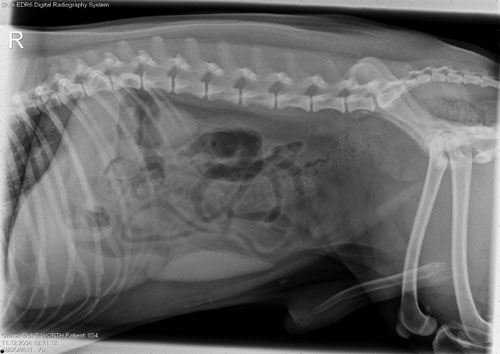

At Village Veterinary Hospital, we strive to provide excellence in diagnostic services for pets in Folsom, Louisiana. A key piece of our array of diagnostic tools is digital radiography. Used to help us diagnose numerous medical conditions, digital radiography goes beyond what we can see and feel during routine physical examinations. It is a painless, safe, completely non-invasive procedure that provides us with high-definition images of internal systems quickly and efficiently.

Using this technology, our veterinarian can assess internal organs such as the heart, lungs, liver and kidneys for disease and conditions such as pneumonia. Additionally, digital radiography is used to inspect areas such as the abdomen and the intestinal tract for foreign objects and obstructions, to detect masses and discover pregnancies. Our doctor can also determine the severity of orthopedic injuries such as breaks and fractures, diagnose chronic arthritis, and certain spinal cord diseases.

Digital radiography provides images much faster and with greater clarity than traditional x-rays. The digital images can be manipulated, enhanced, and contrasted, enabling us to diagnose a condition more accurately.